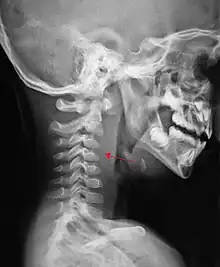

If more than half of the size of the C2 vertebra, it may indicate retropharyngeal abscess.[7]